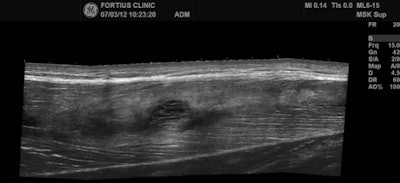

A 24-year-old male professional football player who presented with sudden onset of pain following striking of the ball. Coronal STIR MRI demonstrates focal defect within the left rectus femoris central muscle at the musculotendinous junction (grade II strain). Note the feathery edema pattern within the muscle radiating from the primary injury site.A 24-year-old male professional football player who presented with sudden onset of pain following striking of the ball. Coronal STIR MRI demonstrates focal defect within the left rectus femoris central muscle at the musculotendinous junction (grade II strain). Note the feathery edema pattern within the muscle radiating from the primary injury site. Extended field-of-view ultrasound demonstrates loculated hematoma at the musculotendinous junction with surrounding increased reflectivity within the rectus femoris muscle. Images courtesy of Dr. Justin Lee, Chelsea and Westminster Hospital, London.Extended field-of-view ultrasound demonstrates loculated hematoma at the musculotendinous junction with surrounding increased reflectivity within the rectus femoris muscle. Images courtesy of Dr. Justin Lee, Chelsea and Westminster Hospital, London.